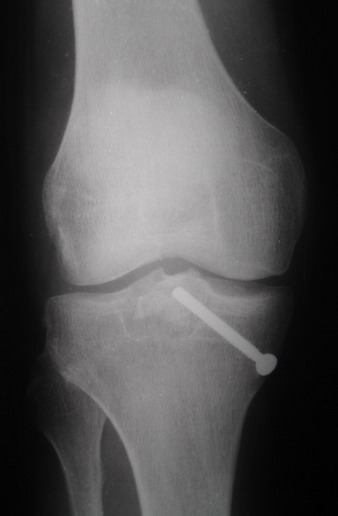

В  3  из  4  случаев  мы  применили  винт,  проведенный ретроградно по

аналогии с фиксацией заднего края большеберцовой кости при переломах в

области  голеностопного  сустава.  В прищепке рентгенограммы одного из

наших  пациетов  до  операции и спустя полгода. Остальные 3 наблюдения

Вложение не в текстовом формате было извлечено…

Имя     : 2.jpg

Тип     : image/jpeg

Размер  : 29521 байтов

Описание: отсутствует

Url     : http://weborto.net:8080/pipermail/ortho/attachments/20070808/782df48f/attachment-0004.jpg